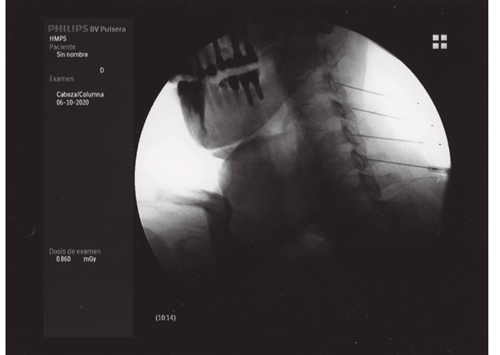

El dolor osteomuscular es la causa más frecuente de consulta en las unidades del dolor; la degeneración artrósica es la patología más prevalente dentro del dolor osteomuscular, siendo las zonas más afectadas la columna vertebral (tanto a nivel lumbar como cervical), las extremidades (rodilla, cadera, hombro), quedando el resto de las articulaciones de la anatomía como localizaciones menos frecuentes. Las técnicas intervencionistas intentan paliar el dolor causado por la artrosis, en muchos casos en pacientes con patología acompañante que hace que la posible solución quirúrgica sea descartada por su excesivo riesgo (prótesis de rodilla o cadera), o bien, como ocurre en el caso de la espondiloartrosis, el tratamiento quirúrgico no garantice la eliminación del dolor, como ocurre con la artrodesis de columna preconizada para tratar este tipo de dolor. Como siempre, la dificultad estriba en poder ofrecer al paciente un tratamiento con evidencia científica suficiente y con el riesgo más bajo posible, que conlleve a un resultado satisfactorio para él. El presente artículo pretende revisar las técnicas intervencionistas disponibles para tratar el dolor causado por la artrosis, y su grado de evidencia cuando esta está disponible.